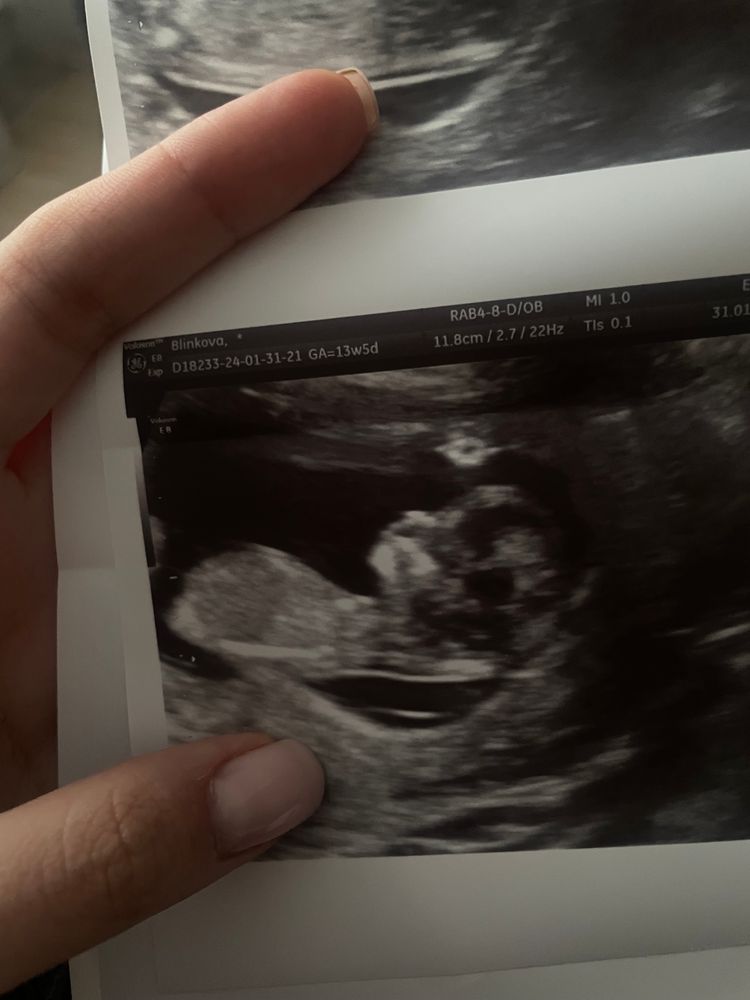

1 скрининг 12 недель ❤️

Поздравляю от всей души🤗 Пусть всё будет хорошо🙏 У нас похожий срок. Прошла первое УЗИ скрининг, сдала НИПТ, жду результат.